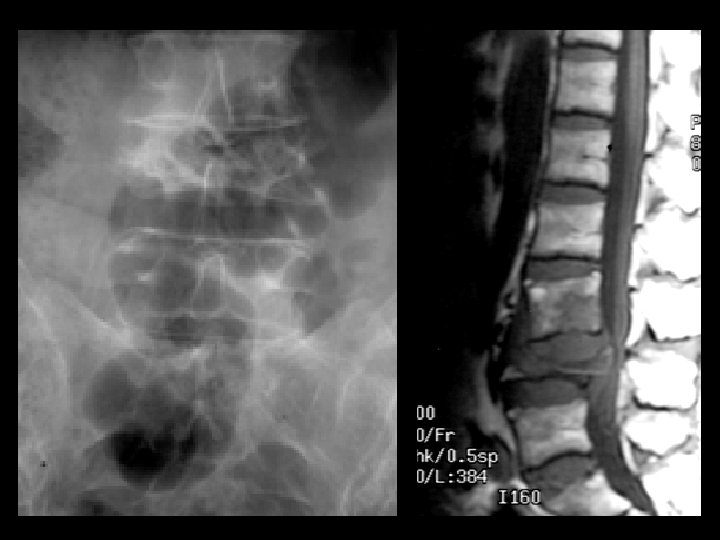

Potts Disease • Findings: – Complete collapse of L 4 and cauda equina compression – Subligamentous soft tissue extension to L 3 body • ddx: – Staph aurius – Gram negatives (IVDA)

Ankylosing Spondylitis • • Findings: – fused SI joints – right hip erosions – lumbar syndesmophytes Sero-negative chronic inflammatory disease Starts in the low back and progesses upward ddx (sacroilitis) – bilateral • ank spond • IBD – Unilateral • Reiter’s • psoriasis